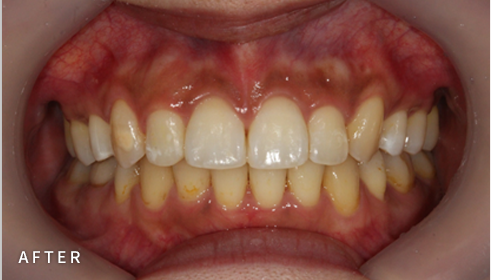

비발치 덧니 교정

덧니고민, 비발치로 교정하세요

악궁 확장, 미니 스크류, 치간 삭제 등 다양한 방법을 활용해 가능한 한

발치를 피하고, 자연스럽고 만족스러운 결과를 얻을 수 있도록

정밀하게 계획하고 진료합니다. 발치 여부가 애매한 경우,

‘레벨링 후 재평가’ 과정을 거쳐 비발치를 우선 고려합니다.